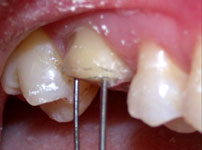

Fig. 4

Determinação do bisel proximal com a ponta diamantada de menor diamêtro (n°1111 da KG Sorensen). Notar a proteção do dente 25 da ação da ponta, com a utilização de matriz de aço dobrada em forma de Z.

Fig. 7

Fios ortodônticos de 0.7 mm inseridos nos orifícios permitindo a visualização do paralelismo ou não após a realização das perfurações.

Para conseguir o paralelismo entre os orifícios, um fio ortodôntico foi inserido na primeira perfuração, o que auxiliava no posicionamento paralelo da broca no momento da realização do segundo orifício e, assim sucessivamente, até a última perfuração (Fig. 7).